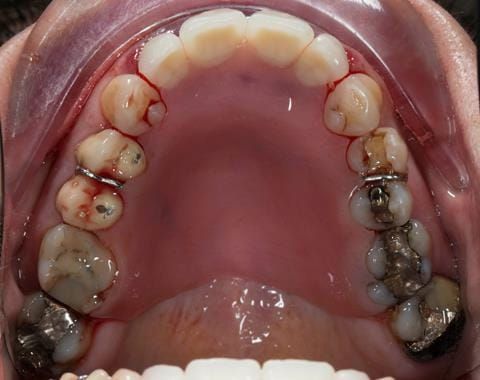

- UR2 peri-radicular periodontitis with a peri-radicular area on the root apex. Retrograde amalgam filling from a previous apicectomy. No visible root canal or root canal filling. Large circumferential marginal gap between the crown and tooth. Large post and core present. Very little tooth structure remaining resulting in a fragile tooth with increased potential for fracture.

- UR1 peri-radicular periodontitis with a small peri-radicular area on the root apex with wide blunderbuss apex. Radio-opaque root canal filling present approximately 3 mm short of the radiographic apex. Large circumferential marginal gap between the crown and tooth. Large post and core present. Very little tooth structure remaining resulting in a fragile tooth with increased potential for fracture.

- UL1 peri-radicular periodontitis with a peri-radicular area on the root apex. Retrograde amalgam filling from a previous apicectomy. Visible root canal space with no sign of root canal filling. Large circumferential marginal gap between the crown and tooth. Large post and core present. Very little tooth structure remaining resulting in a fragile tooth with increased potential for fracture.

- UL2 peri-radicular periodontitis with a peri-radicular area on the root apex. No visible root canal or root canal filling. Large circumferential marginal gap between the crown and tooth. Large post and core present. Very little tooth structure remaining resulting in a fragile tooth with increased potential for fracture.

- Other than the maxillary incisors the remaining dentition was in marginally better condition being moderately to heavily restored. Many will probably require replacement and restoration from time to time mainly from wear and tear owing to occlusal forces.